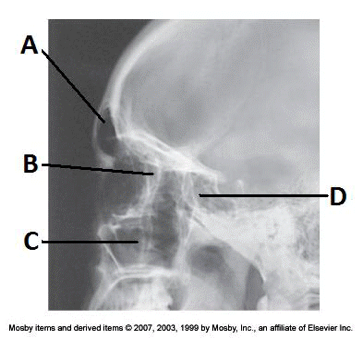

4. Examine the image of the paranasal sinuses below. The letter D labels the:

a. maxillary sinuses

b. ethmoid sinuses

c. sphenoid sinuses

d. frontal sinuses

__ 7. Examine the image of the paranasal sinuses below. The letter B labels the:

a. ethmoid sinuses

b. sphenoid sinuses

c. maxillary sinuses

____ 13. Examine the image of the paranasal sinuses below. The letter A labels the:

a. sphenoid sinuses

b. frontal sinuses

c. ethmoid sinuses

d. maxillary sinuses

bb. frontal sinuses

____ 61. Examine the image of the paranasal sinuses below. The letter C labels the:

a. petrous ridge

b. vomer

d. condyle of the mandible

aa. petrous ridge